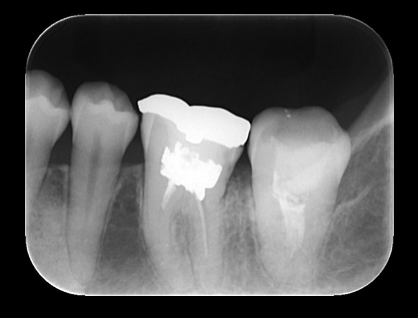

根管治療前のデンタルX線写真